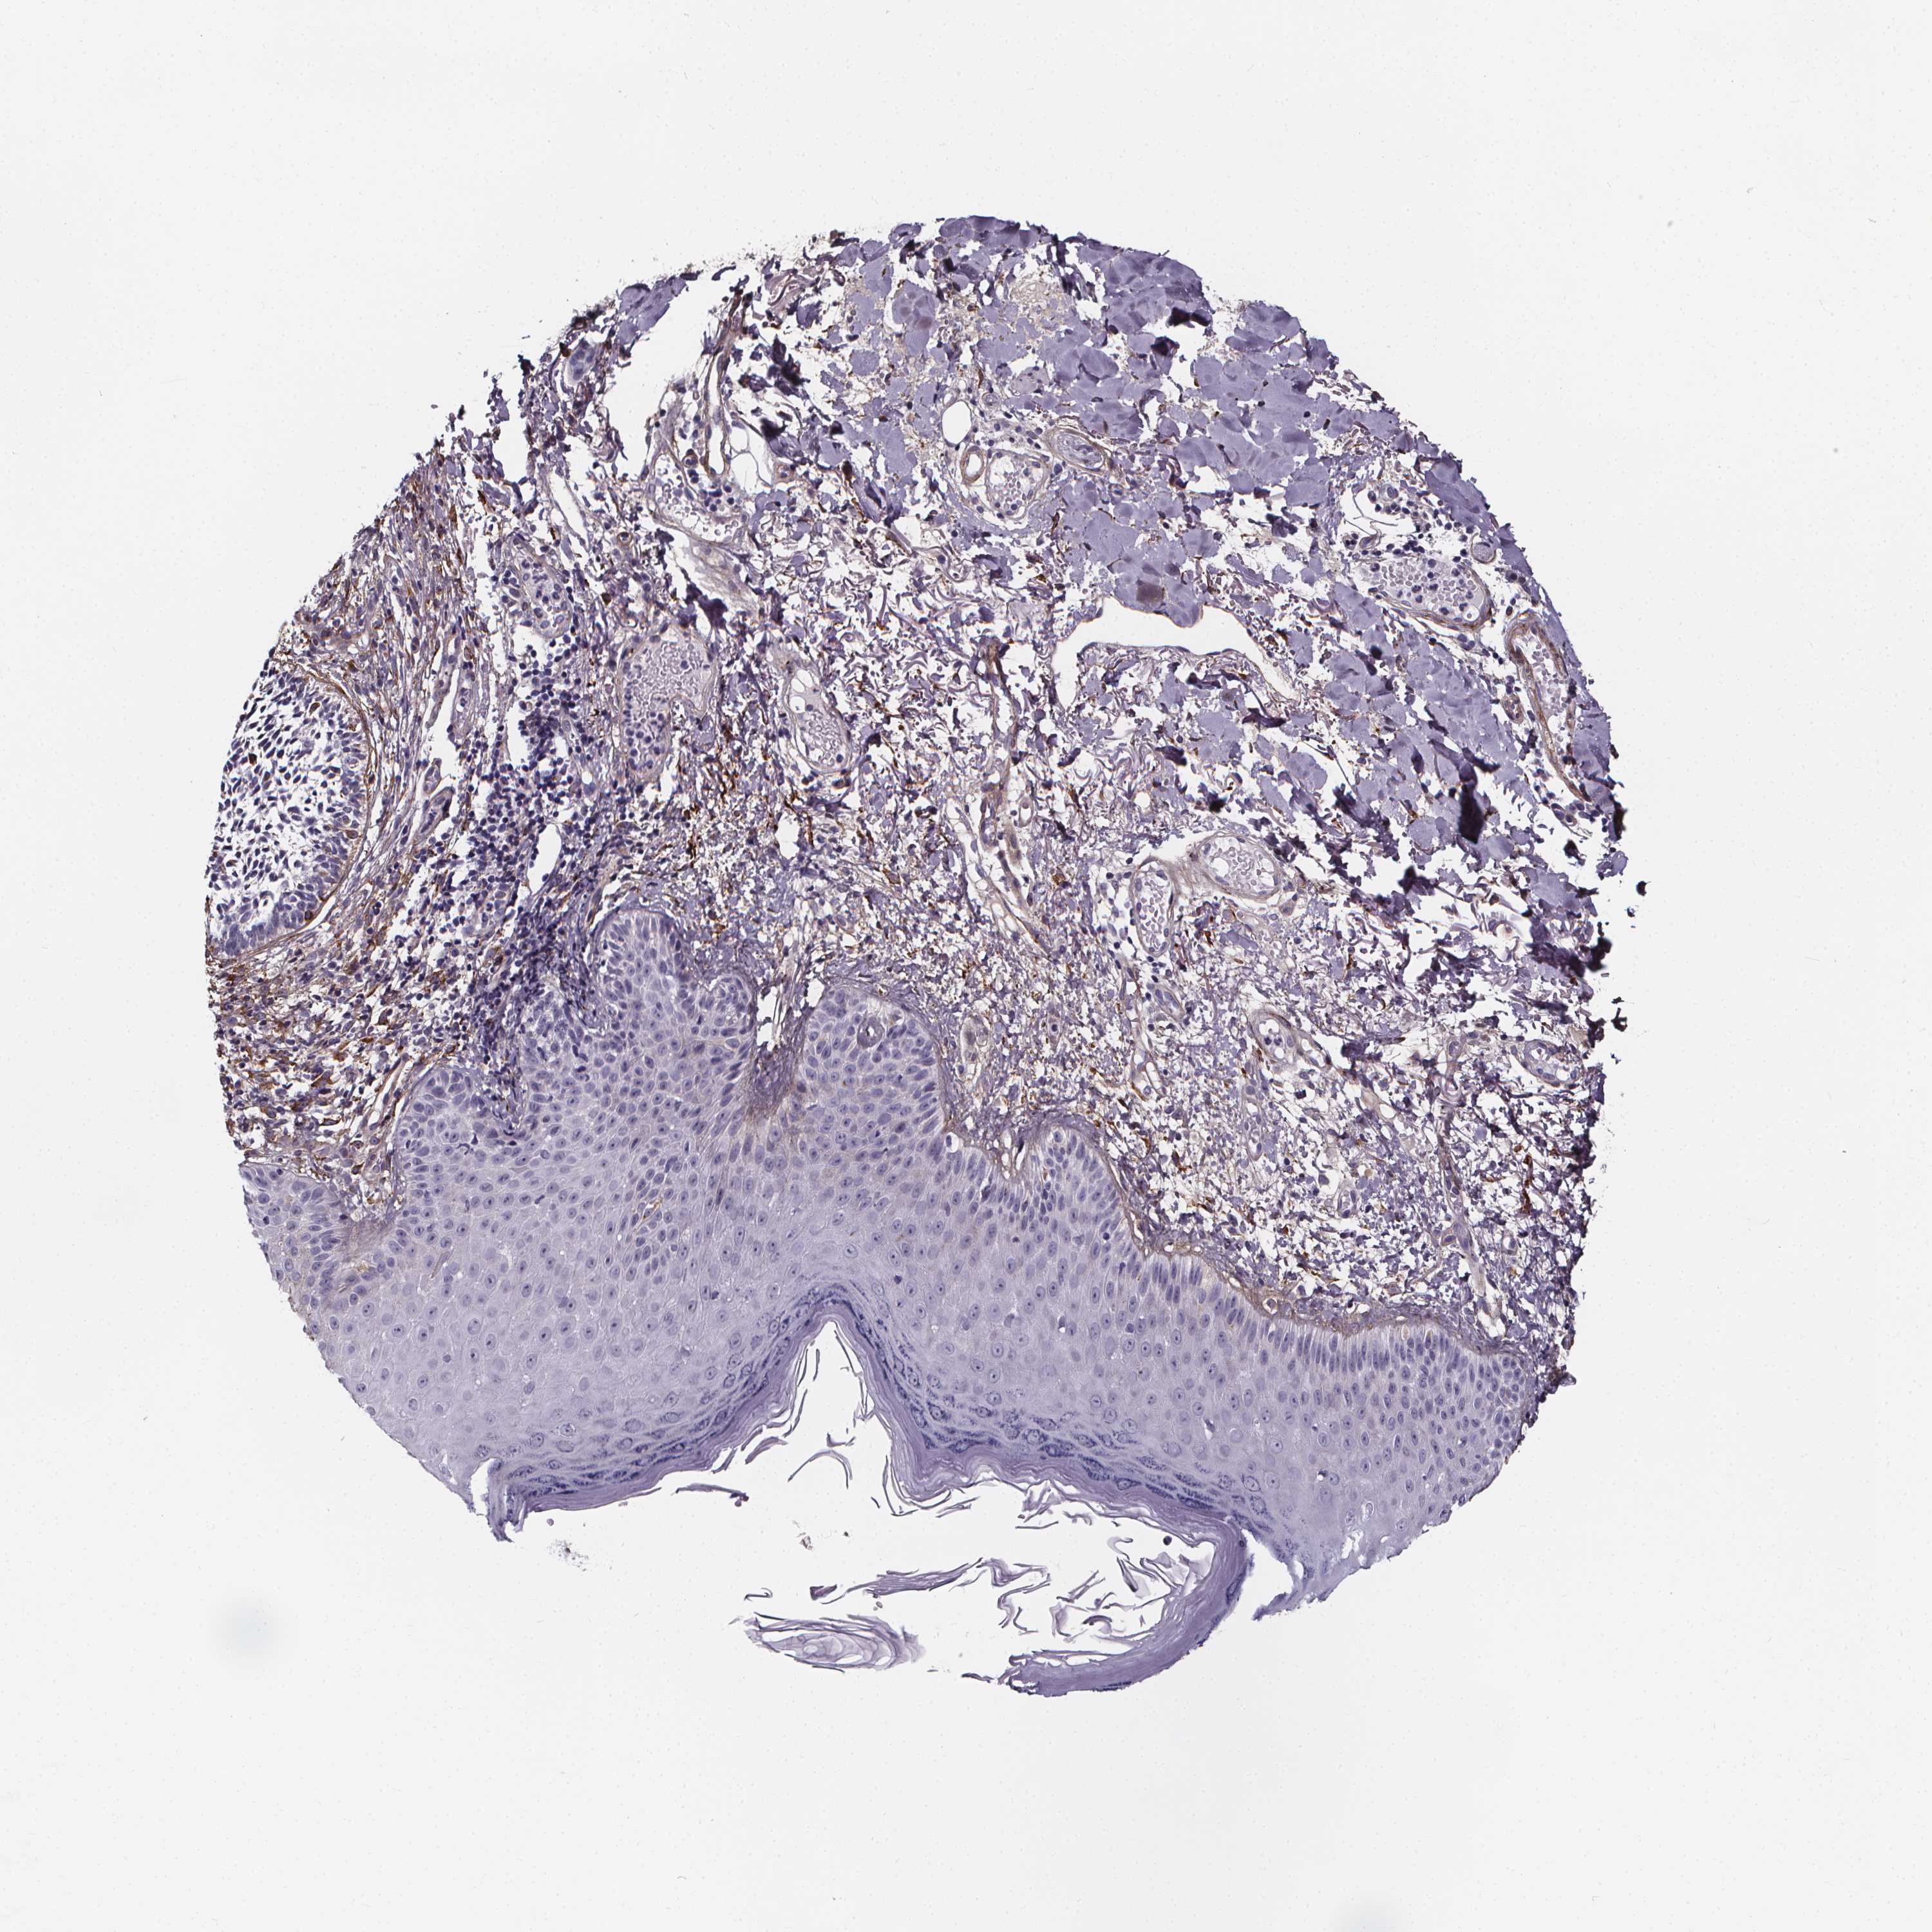

CANCER SKIN CANCER Show tissue menu

Basal cell and squamous cell cancer

SKIN CANCER - Protein expressioni

A mouse-over function shows sample information and annotation data. Click on an image to view it in a full screen mode. Samples can be filtered based on level of antibody staining by selecting one or several of the following categories: high, medium, low and not detected. The assay and annotation is described here.

Each image is clickable and will lead to virtual microscopy that enables deeper exploration of all samples and also displays staining intensity scores, fraction scores and subcellular localization as well as patient and tissue information for each sample.

Antibody HPA063595

Basal cell carcinoma